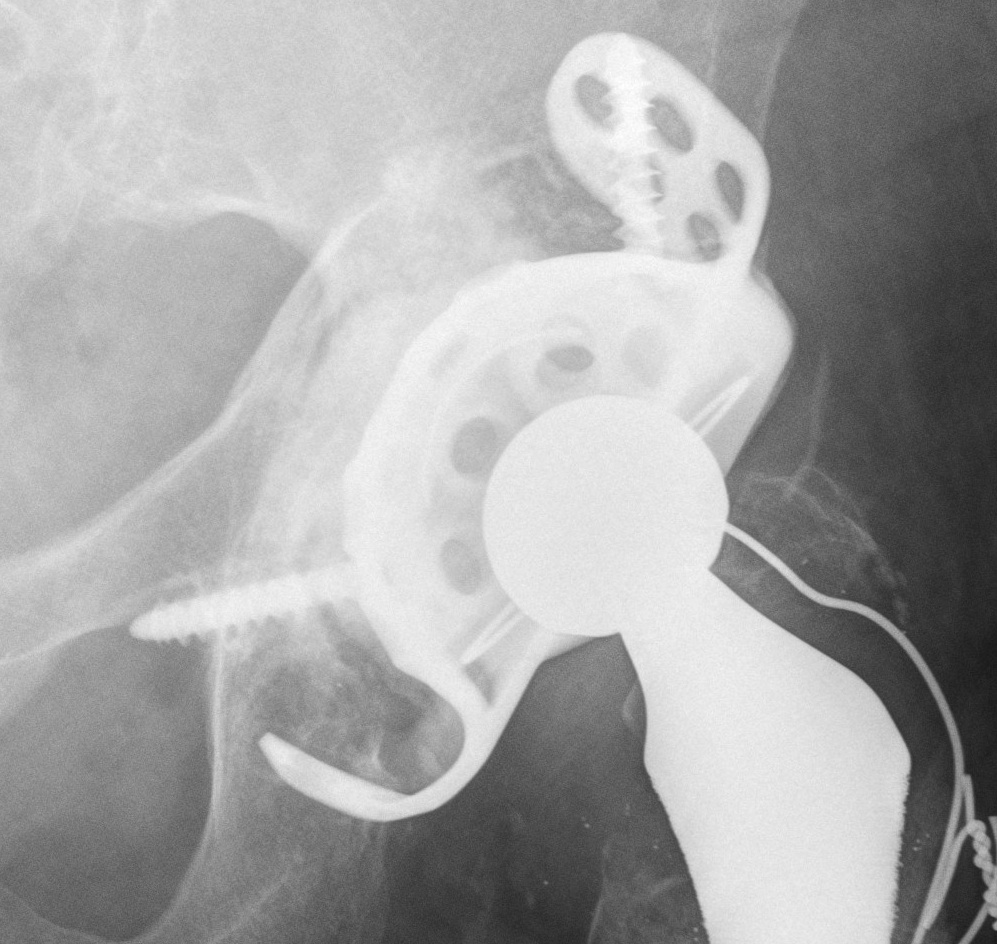

A. Allograft + Antiprotrusio Cages + Cemented Cup

Types

- Ganz / Muller / Burch Schneider

- variations on them

- hook or screws into ilium

- hook or screws onto ischium

- can have extension for screws onto pubis